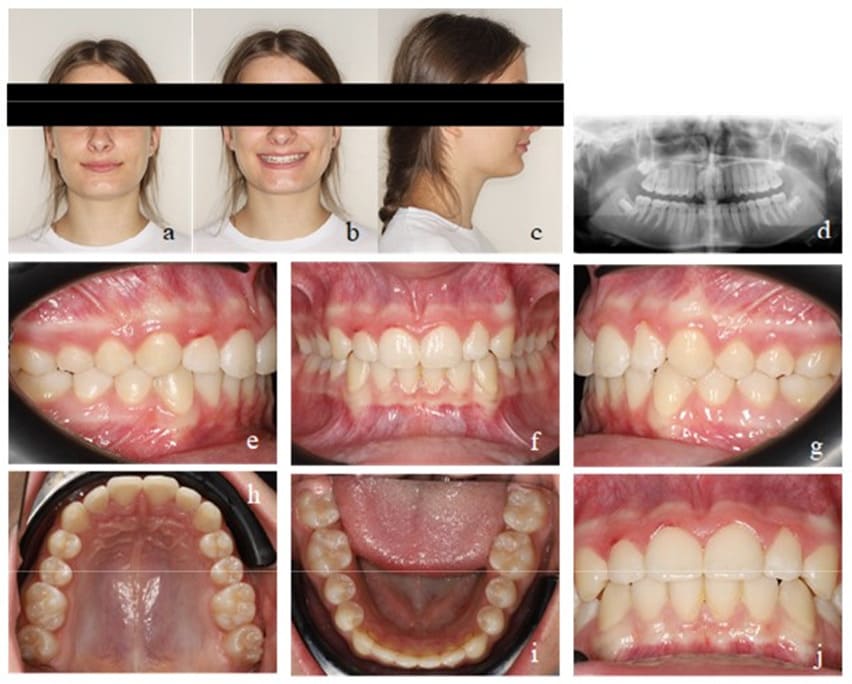

During all treatment phases, the patient had been highly compliant and motivated. 18 months of active mykie®-treatment showed significant improvements on the dental as well as on the myofunctional side. To ensure a stable retention of what was achieved, the patient continued wearing an EGA on a nightly basis throughout the transitional phase of dentition until all second molars erupted and visited the orthodontic office biannually. No further orthodontic treatment was necessary (Figure 8). Finally, for perfect alignment, a short aligner treatment could be recommended (Figure 9).

Figure 8: Case 1. Final findings. Frontal view of the occlusion (b), occlusion right (a) and left (c). Upper (d) and lower arch (e).

Figure 9: Case 1. Final findings after a short Invisalign® treatment. En face (a, b) and profile of the patient (c). Final Panoramic x-ray (d). Frontal view of the occlusion (f), occlusion right (e) and left (g). Upper (h) and lower arch (i). View of the final overjet and overbite (j).